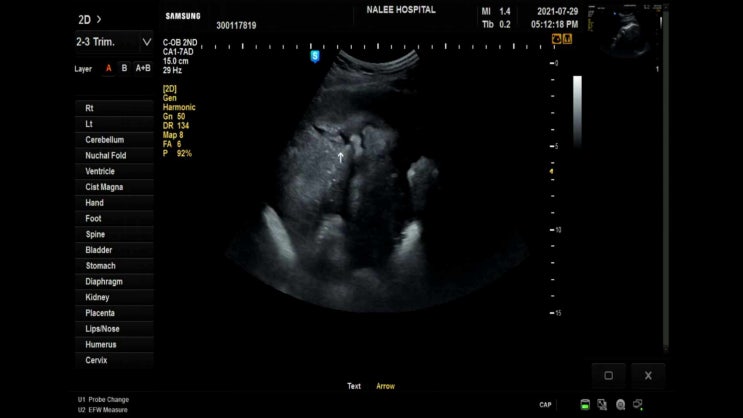

20210729 36주차 10개월 언제나와도 이상하지 않은

어느덧 임신 10개월차에 들어섰다 오늘로 회사도 마지막 8월부터 출산휴가 시작이다 확실히 만삭이 되니 몸...